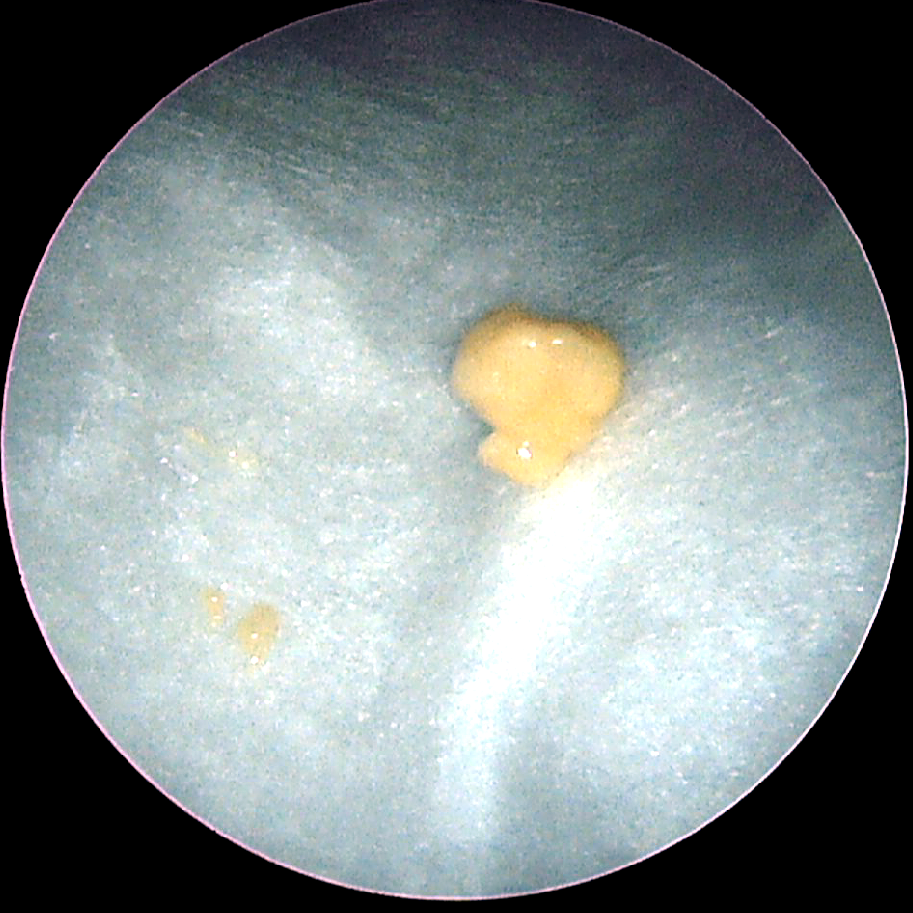

눈에 보이고 있던 것은 2 밀리미터 정도였지만, 실제로는 1 센티미터 가까운 결석이었습니다. 이름이 돌이지만, 실제로 돌처럼 딱딱한 경우는 드물고, 손으로 누르면 걸쭉하게 부서지는 치즈 같은 느낌입니다. 굳었을 때 엄청난 악취가 손에 묻기 때문에 깜짝 놀랄 정도입니다.

편도 결석이 빠진 곳을 자세히 보시면 위에 사진처럼 깊은 구멍이 남아있어요 이런 곳을 편도음와(tonsillar crypt)라고 하는데 편도음와에 음식, 침, 후비루 등이 쌓여서 굳으면 편도결석이 되는 것입니다. 환자에게 있어서는 치석이 붙는 것과 같은 원리이며, 균등한 치아보다 어긋난 치아 사이에 치석이 더 많이 나지 않느냐고 설명하면 잘 이해할 수 있습니다. 이미 생긴 편도 음와를 제거하는 방법은 수술뿐이지만, 편도 음와에 결석이 잘 들어가지 않도록 예방하는 방법은 있거든요. 편도선와에 음식물, 침, 후비루 등이 쌓이지 않도록 식사 후 양치질을 할 때마다 목 깊숙이 편도를 씻어내는 듯한 느낌으로 양치질을 하는 것입니다. 살균되는 성분이 섞인 가글일 필요는 없습니다. 움푹 패인 부분을 씻어 내는 것이 목적이기 때문에 수돗물로 충분합니다.